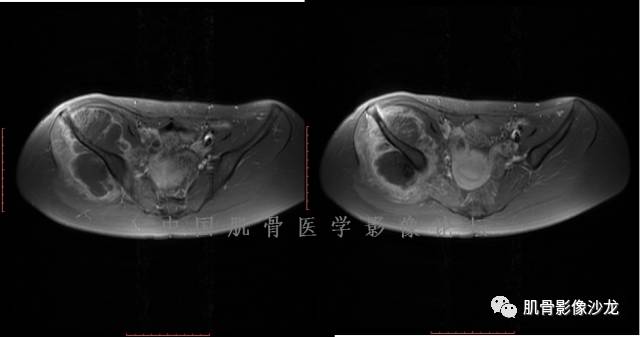

阳光明媚 :股骨远端前部可见片状长T1、长T2不均信号影,压脂序列呈不均高信号影,平片无明显钙化,边界清。内有纤维、粘液,

雪舞 : 股骨下端,皮质下偏心性溶骨性破坏,分叶状,T2混杂高信号。无明显软组织肿块。X片未见异常。

雪舞 :第二例,位于骶骨,有骨质破坏并有软组织肿块,软组织肿块边界清

雪舞: 第二例我们能够看到破坏与软组织肿块不成比例,软组织肿块大,破坏小

雪舞 :第二例挺难的,骨质破坏是溶骨性的,局部皮质中断,软组织肿块外缘光滑